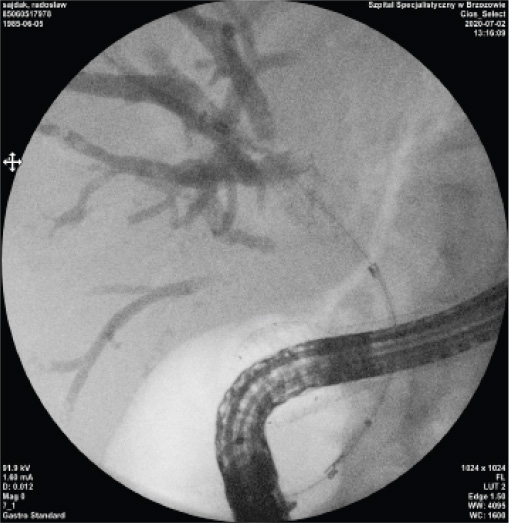

Case Presentation 2

I also suggest the use of BMCL stents in patients in whom it would be very difficult to reach the Vater’s papilla area, due to the high dynamics of the neoplastic process. For example, a 35-year-old patient with inoperable biliary tract tumor and a clogged duodenum due to NPL infiltration, with plastic stents used previously, theoretically without any possibility of replacing them with new ones.

7. Clogged plastic stents and visible implanted duodenal stent (first stage of the procedure).

9. The moment of stent expansion with clearly visible middle and distal markers.

8. X-ray picture.

10. X-ray picture.

In the first stage, a duodenum stent was placed. A week after the duodenal stent was placed, the descending part and the papilla region were reached through the duodenal stent and a BMCL stent was placed into the biliary tract. The cross-over biliary and duodenal stents enable the correct drainage of the bile and the movement of food content into the digestive tract.